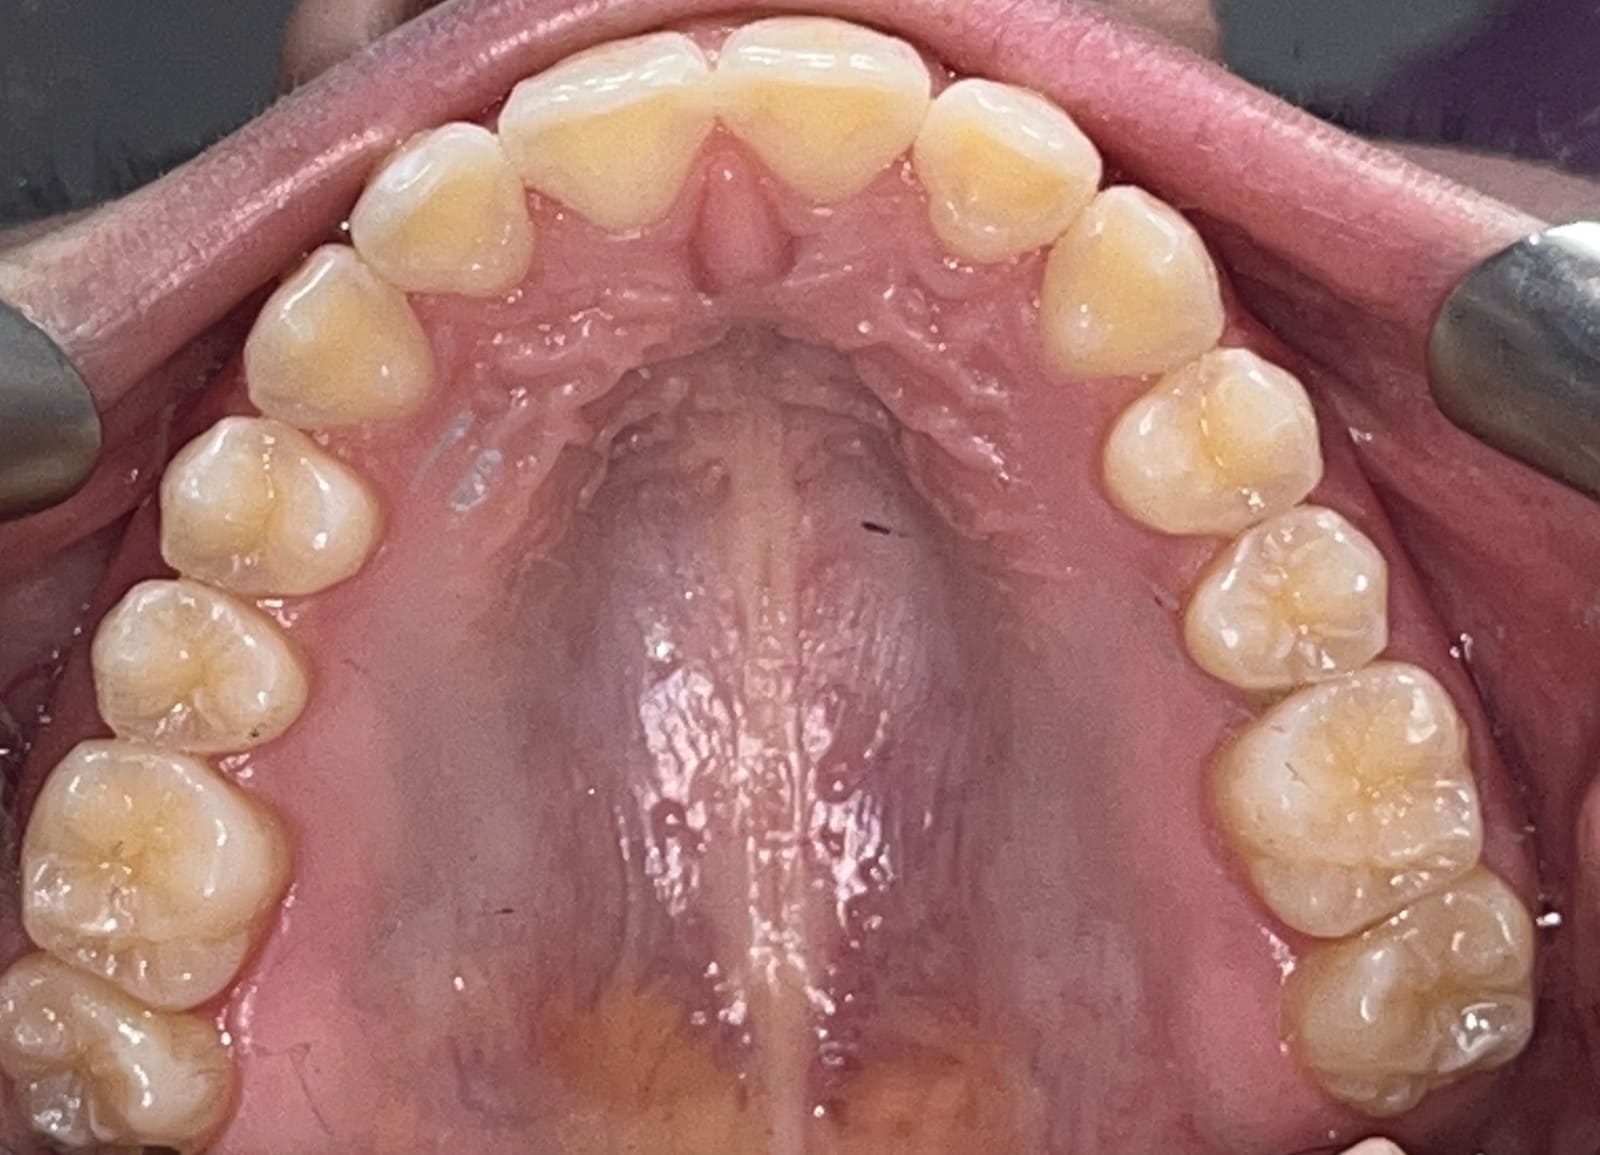

Final